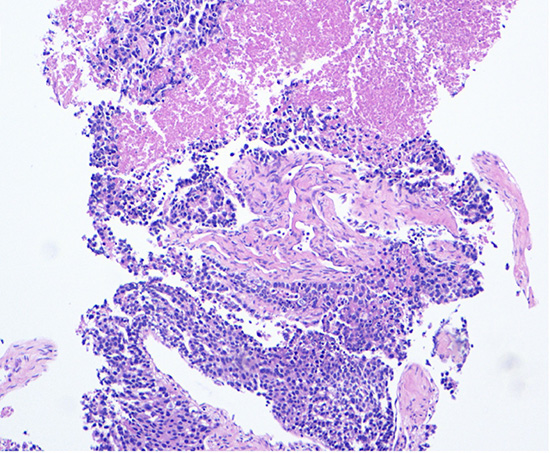

Figure 1. Hematoxylin and eosin stain (10x magnification) of the liver biopsy demonstrating an infiltrative, cellular lesion with predominantly solid growth and areas of tumor necrosis.